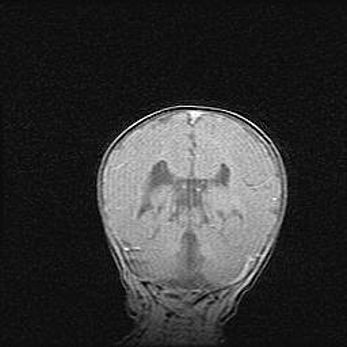

Лейкомаляция с кистозно-глиозной дегенерацией головного мозга.

Возраст: 2 месяца 25 дней

Вес: 6400 г

Окружность головы: 40 см

Срок гестации: 41 неделя

Лейкомаляцию относят к ишемически-гипоксическим повреждениям головного мозга, диагностируемым у новорожденных. При лейкомаляции в головном мозге обнаруживают очаги некроза, возникшие после тяжелой гипоксии и нарушения кровотока. В процессе морфогенеза очаги проходят три стадии: 1) развития некроза, 2) резорбции и 3) формирования глиозного рубца или кисты. Перивентрикулярная лейкомаляция (ПЛ) встречается примерно в 12% случаев среди новорожденных, обычно – у недоношенных детей, причем, частота ее зависит от массы, с которой младенец появился на свет. Наибольшее число малышей страдает лейкомаляцией, если масса при рождении 1500-2500 г.